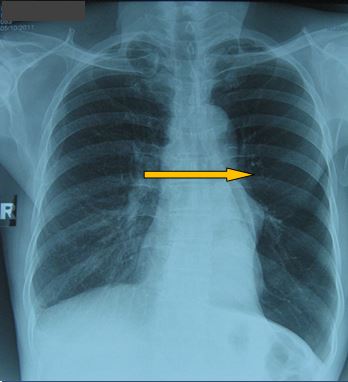

-          X- Quang tim phổi thẳng có hình ảnh đám mờ toàn bộ thùy trên phổi trái:

Trước điều trị

Tổn thương đám mờ toàn bộ vị trí thuỳ trên phổi trái